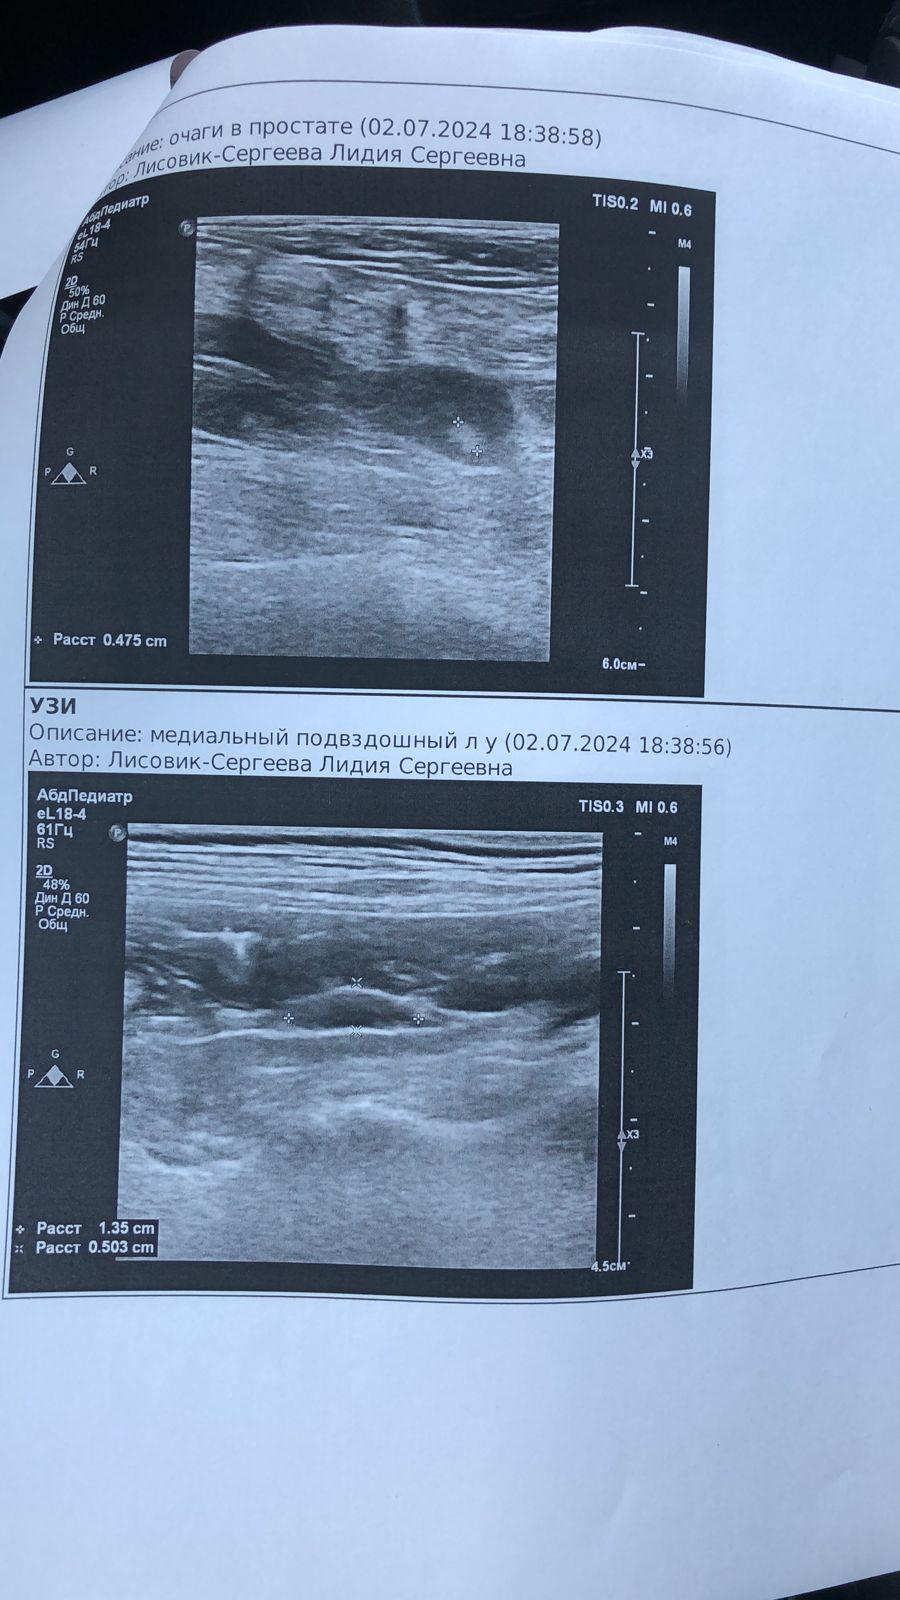

Поездка к онкологу и на УЗИ

IMG-20240702-WA0025.jpg

IMG-20240702-WA0023.jpg

IMG-20240702-WA0024.jpg

IMG-20240702-WA0022.jpg

IMG-20240702-WA0021.jpg